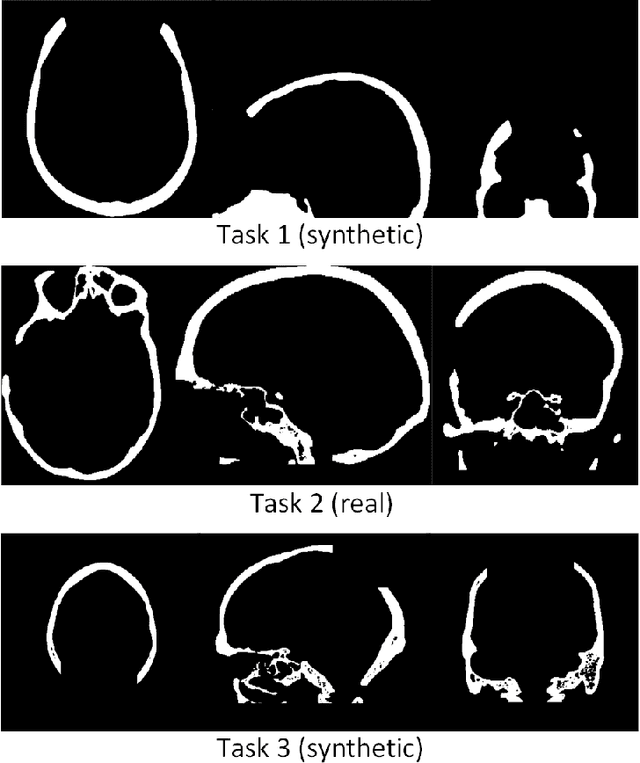

Abstract:The goal of this work is to propose a robust, fast, and fully automatic method for personalized cranial defect reconstruction and implant modeling. We propose a two-step deep learning-based method using a modified U-Net architecture to perform the defect reconstruction, and a dedicated iterative procedure to improve the implant geometry, followed by automatic generation of models ready for 3-D printing. We propose a cross-case augmentation based on imperfect image registration combining cases from different datasets. We perform ablation studies regarding different augmentation strategies and compare them to other state-of-the-art methods. We evaluate the method on three datasets introduced during the AutoImplant 2021 challenge, organized jointly with the MICCAI conference. We perform the quantitative evaluation using the Dice and boundary Dice coefficients, and the Hausdorff distance. The average Dice coefficient, boundary Dice coefficient, and the 95th percentile of Hausdorff distance are 0.91, 0.94, and 1.53 mm respectively. We perform an additional qualitative evaluation by 3-D printing and visualization in mixed reality to confirm the implant's usefulness. We propose a complete pipeline that enables one to create the cranial implant model ready for 3-D printing. The described method is a greatly extended version of the method that scored 1st place in all AutoImplant 2021 challenge tasks. We freely release the source code, that together with the open datasets, makes the results fully reproducible. The automatic reconstruction of cranial defects may enable manufacturing personalized implants in a significantly shorter time, possibly allowing one to perform the 3-D printing process directly during a given intervention. Moreover, we show the usability of the defect reconstruction in mixed reality that may further reduce the surgery time.